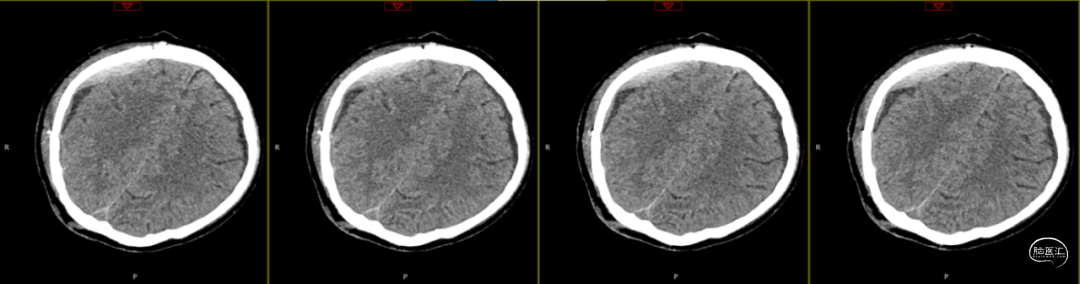

因患者局部头皮逐渐膨隆,且头皮疼痛,于术后89天再次入院。体查可触及头皮下异常物质存在,考虑头皮下积脓并硬膜外脓肿可能,患者无发热,血常规、C反应蛋白、降钙素原等感染指标均为在正常范围。

第1次术后88天,即第2次入院前1天复查(如上图),经反复沟通病情,病人及家属仍拒绝去除骨瓣清创手术,但同意进行手术清创。术中见右侧额部皮下炎性肉芽组织增生,伴有少量分泌物流出,骨瓣下见乳白色脓性分泌物,未闻及明显异味,收集脓性液体送细菌培养、涂片检查,局部硬膜增厚,较多炎性增生组织于局部硬脑膜黏连紧密,缓慢刮除局部异常增生组织后,低功率双极电凝行硬脑膜止血,骨瓣可见右侧额部外板局部被侵蚀,清理表面异物后,使用双氧水浸泡冲洗,并浸入碘伏液中消毒;彻底清除硬膜外、骨缘及右侧额部皮下增生异常组织,额顶部愈合不良刀口予以局部清创,反复使用双氧水及稀释后碘伏溶液冲洗创面,更换钛板及钛钉,还纳骨瓣并固定,皮下留置负压引流管1根,缝合逐层。术后使用万古霉素静脉抗炎治疗,留取术中脓性分泌物进行细菌培养及涂片检查(培养及检验均呈阴性)。

第2次术后第1天复查颅脑CT资料(第1次术后92天)(如上图)。